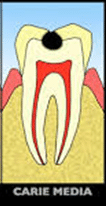

Quando si parla di carie questo concetto è ancora più importante perché, purtroppo, dalla carie non si guarisce.

In che senso ti starai chiedendo, te lo spiego subito: se prendi un raffreddore, l’influenza o la bronchite, quando guarisci non hai più la malattia, torni sano. Nel caso della carie invece, per curarla, bisogna rimuovere la parte di dente ammalata e fare un otturazione. La carie non c’è più è vero ma il dente non è tornato sano ha “ un buco chiuso con un materiale specifico”.

La parte del dente che mastica è formata da punte ( cuspidi ) e solchi. Quando si mastica il cibo schiacciato dai denti rimane intrappolato nei solchi, soprattutto cibi come cereali, crackers, biscotti, cioccolata, tutti alimenti, tra l’altro molto consumati dai bambini.

Rimuovere questi alimenti dal dente con lo spazzolino non è sempre facile per tre motivi, il primo è che sono residui molto consistenti e le setole fanno fatica a rimuoverli, il secondo è che i solchi molte volte sono stretti e le setole proprio non entrano in profondità a sufficienza per rimuovere il cibo in profondità, il terzo è dovuto al fatto che i bambini hanno difficoltà tecniche ad eseguire un corretto lavaggio dei denti. Quello che succede è che la parte del dente che mastica si caria proprio in età infantile.